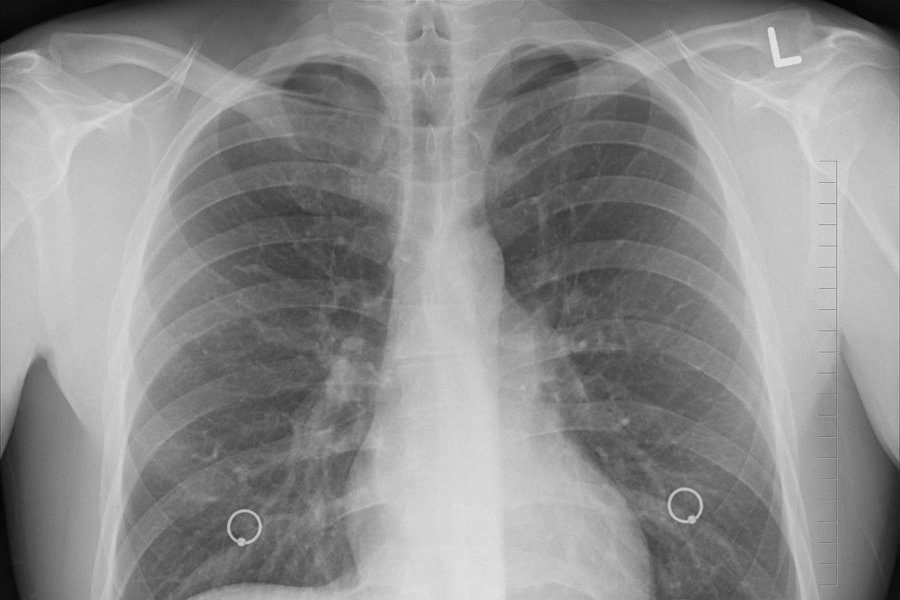

В клиниках Москвы начала работать разработанная в Калуге технология комплексного анализа компьютерной томографии органов внутри грудной клетки с применением искусственного интеллекта, сообщает ТАСС.

Она позволяет проводить анализ компьютерных томографий и обнаруживать признаки 7 различных патологий, включая опухоли, коронавирус, травмы позвоночника, жидкость в плевральных областях, ишемическую болезнь сердца, аневризму аорты и расширение легочного ствола.